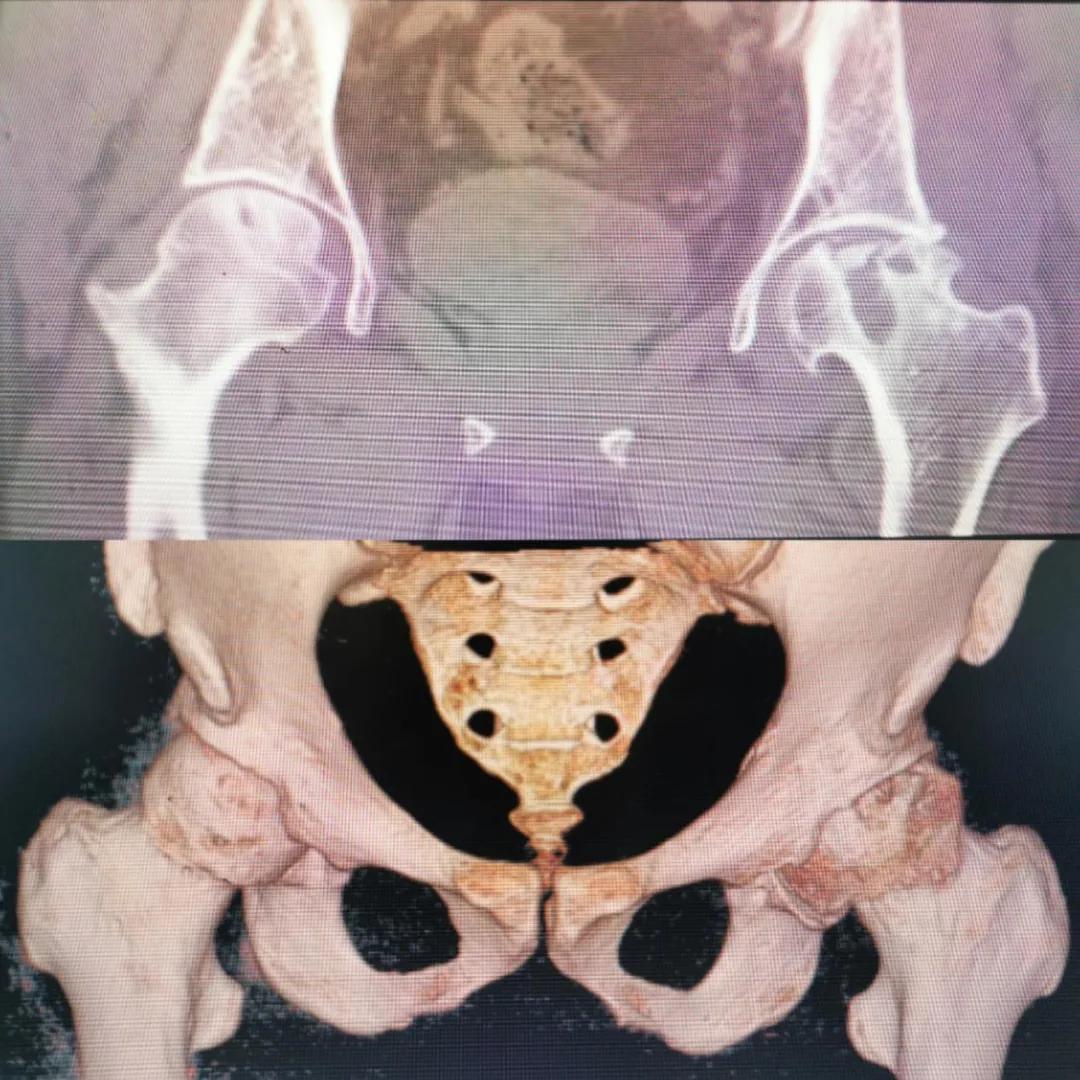

入院急查血結(jié)果提示炎癥反應(yīng),感染較重,凝血功能及肝功均不同程度損害;髖關(guān)節(jié)磁共振(MRI)檢查提示雙側(cè)股骨頭缺血壞死,繼發(fā)髖關(guān)節(jié)炎,左側(cè)髖周軟組織腫脹。醫(yī)療團(tuán)隊(duì)給出的初步診斷為膿毒血癥、股骨頭缺血性壞死、軟組織感染、皮膚潰瘍及閉孔神經(jīng)損傷。

圖片(圖為患者入院時髖部CT檢查)

追溯病史,患者訴前不久曾用蜂蜇療法治療股骨頭壞死,每日4次,每次100只蜜蜂蜇雙臀部、髖部,這才導(dǎo)致了病情急劇進(jìn)展。查明了來龍去脈,我院智能微創(chuàng)骨科醫(yī)護(hù)團(tuán)隊(duì)與患者家屬積極溝通病情,給予特殊級抗生素抗感染以及消腫、止痛等支持治療,同時對潰瘍創(chuàng)面進(jìn)行專業(yè)、規(guī)范的清創(chuàng)、換藥處理,保護(hù)創(chuàng)面降低感染程度;護(hù)理上輔助翻身,減少壓力性損傷。